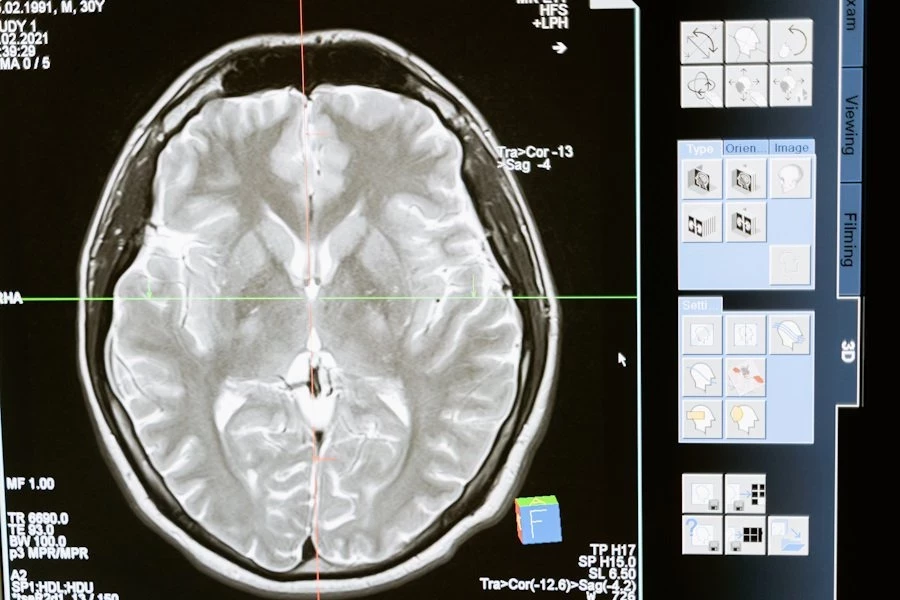

Головной мозг, наша самая сложная «компьютерная» система, подвержен воздействию многих факторов, и его работа остается загадкой. В нем содержится около 100 млрд нейронов, каждый из которых связан с другими посредством синапсов, создавая замысловатую паутину. Мозг способен выполнять операции со скоростью от 1012 до 1028 FLOPS/сек, в то время как самый быстрый суперкомпьютер 2022 года работает с мощностью 1,6 Х 1018 FLOPS/сек, сообщает ТАСС.

Проблемы с мозгом могут проявляться различными способами: от общих симптомов, таких как слабость и головные боли, до конкретных функциональных нарушений, таких как нарушения речи или координации движений. К примеру, недавно «Определены участки генома, связанные с ускоренным развитием деменции».

По данным неврологов, мозг чувствителен к воздействию различных факторов, включая алкоголь и курение, но наиболее вредными являются дефицит кислорода и глюкозы в крови. Нейроны в мозгу зависят от поступления глюкозы через кровь, и при отсутствии кровообращения они начинают умирать в течение пяти минут. Стресс также влияет на мозг, меняя химический баланс и передачу сигналов.